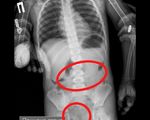

Samarqandlik shifokorlar bemor qornidan 200 gramm mix oldi

Samarqandda noyob jarrohlik amaliyoti muvaffaqiyatli o‘tkazildi